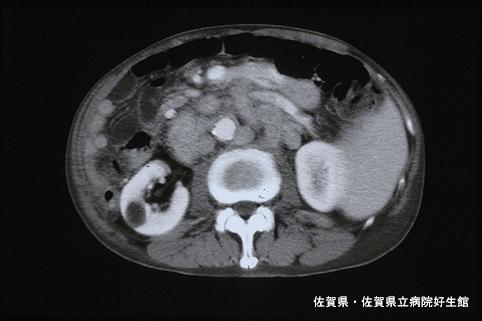

A case of type 4 (diffuse infiltrated type) advanced cancer of the sigmoid colon with various pathological findings.

Saga Pref., Saga Prefectural Hospital Koseikan (Dr.下田ら)

[ Image ID:4603 ]

Malignant epithelial tumor/Adenocarcinoma

Technique, Method

CT